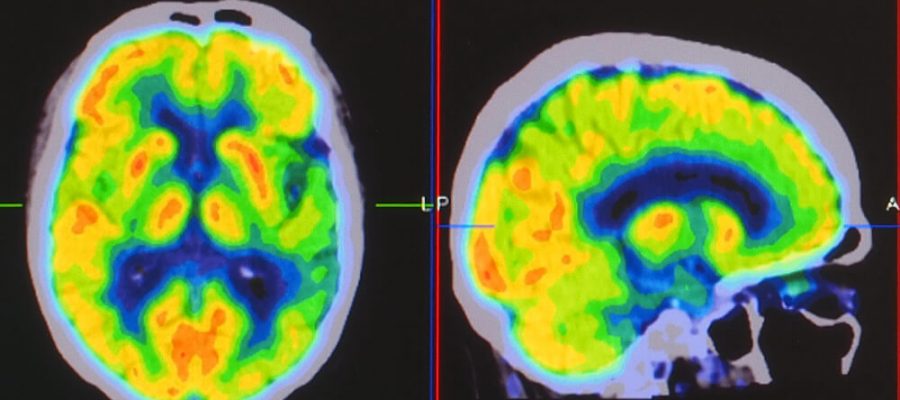

Perfüzyon mr, radyoloji kategorisinde yer alan bir görüntüleme yöntemidir. Özel bir görüntüleme yöntemi olarak tercih edilir ve beyindeki kan akışının ne kadar olduğunu öğrenmek amacıyla kullanılır. Bu teknik ile kan akışının miktarını ölçmek mümkündür. Uzman doktorlar tarafından yaygın bir şekilde tercih edilir. Radyasyon içermediği için de bunun bir sakıncası yoktur.

Beyindeki kan akışı ve meydana gelen kan birikimi, sağlık açısından çok önemlidir. Bunun izlenmesi ve incelenmesi içinse perfüzyon MR çekilmesine gerek duyulur. Bu izleme ve inceleme işlemi için damardan kontrast madde veriliyor.

Görüntüleme tekniklerinin gelişmesi, MR yöntemlerinin daha faydalı ve kaliteli olmasını sağlıyor. Beyin içinin görüntülenmesinde en fazla kullanılan işlemlerden birisidir. Aynı zamanda beyinde kan akışı ve birikimi için ölçüm amacıyla kullanılır.

Perfüzyon MR yöntemi ile beynindeki kan birikimi ve kan akış hızı kolay bir şekilde görülebiliyor. Aynı zamanda beyin tümörlerinin konumunun belirlenmesinde de işe yarar. Kişinin beyninde damar tıkanıklığı olması durumunda bunu tespit etmek için de istenir.